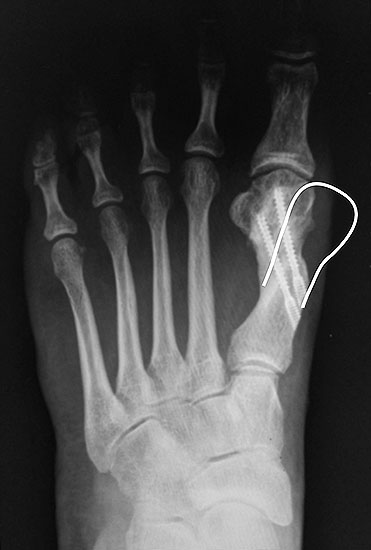

Präoperatives Röntgenbild Fuß d.p. mit eingezeichneten Winkeln. A) Intermetatarsalwinkel, B) Hallux valgus Winkel, C) Interphalangeal-Winkel.

Abbildung 2

• Operationsplanung anhand der Röntgenaufnahmen unter Beachtung wichtiger radiologischer Landmarks wie Intermetatarsalwinkel, Hallux valgus – Winkel, distaler Gelenkflächenwinkel (Distal Metatarsal Articular Angulation - DMAA), Metatarsaleindex und Sesambeinposition (Abb. 2).